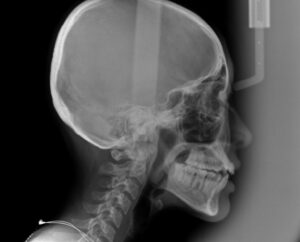

🔶矯正開始時レントゲン🔶

精密検査は

スキャナーのトリオスで

歯並びをスキャンして

どれだけ前歯が出ているか調べる

セファロというレントゲン撮影

結果を分析すると